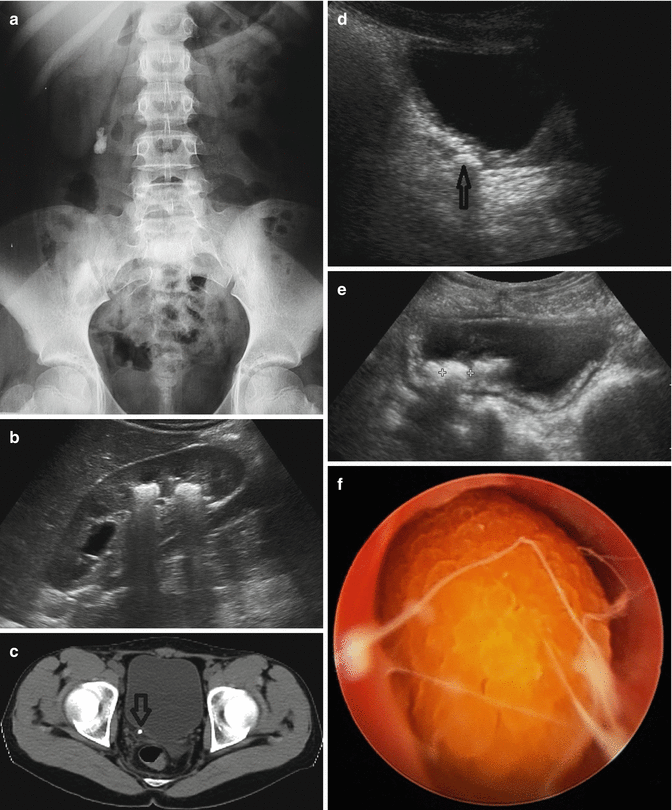

A Extensive Pelvic Nephrolithiasis Between Arrows Due To Uric